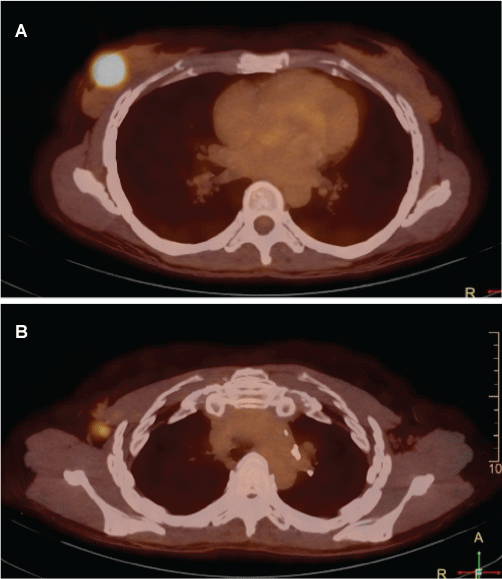

A PET-CT was performed to evaluate the stage of the disease and showed two images with increased FDG uptake, corresponding to the primary lesion in the breast and one lymph node in ipsilateral axila (Figure 3a and Figure 3b).

Figure 3: 18F-FDG PET/CT evidencing two images with increase FDG uptake. The abnormality in the breast was suggested to be the primary lesion (a) and only one lymph node was found in the ipsilateral axilla (b).